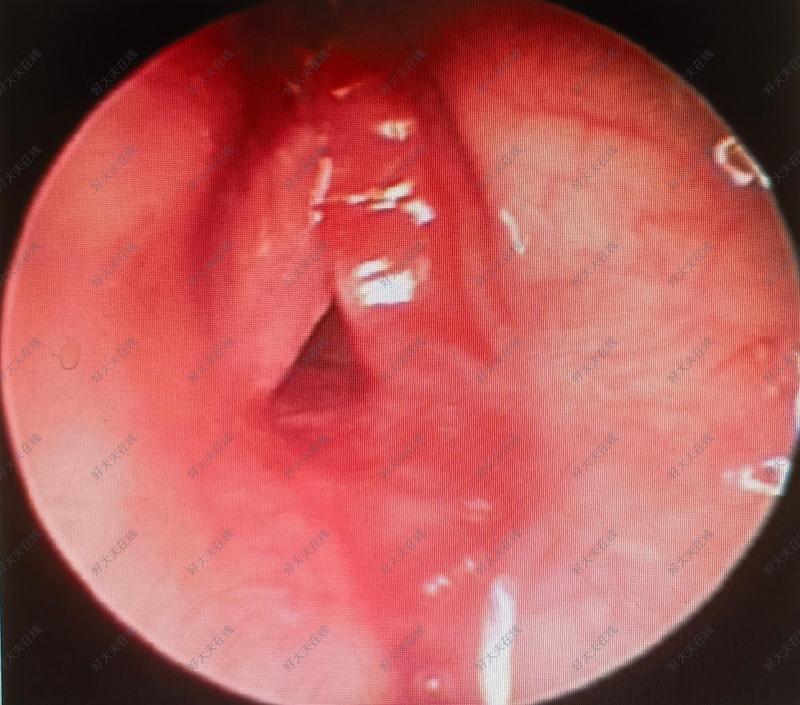

双声带麻痹声门下狭窄

声门下狭窄是指声门下区气道的病理性狭窄。它可能由多种原因引起,如先天性喉部畸形、喉部创伤、炎症、长期气管插管等。主要症状包括声音嘶哑、呼吸困难等。治疗方法包括手术治疗、扩张治疗等,具体治疗方案需根据患者的具体情况而定。今天,为一个刚出生20天的小宝宝进行了气管滑行术!这个手术,可以说是新生儿喉部手术的天花板,国内能开展该类手术的医生寥寥无几!在麻醉师的全力配合下,手术团队的精心操作下,小宝贝手术顺利,术后安全返回新生儿重症监护病房。手术之前,小宝宝只能通过呼吸机支持维持生命,手术的成功,提示小宝宝讲开启新的人生,待切口愈合后,将脱离呼吸机,和正常孩子一样呼吸新鲜空气!